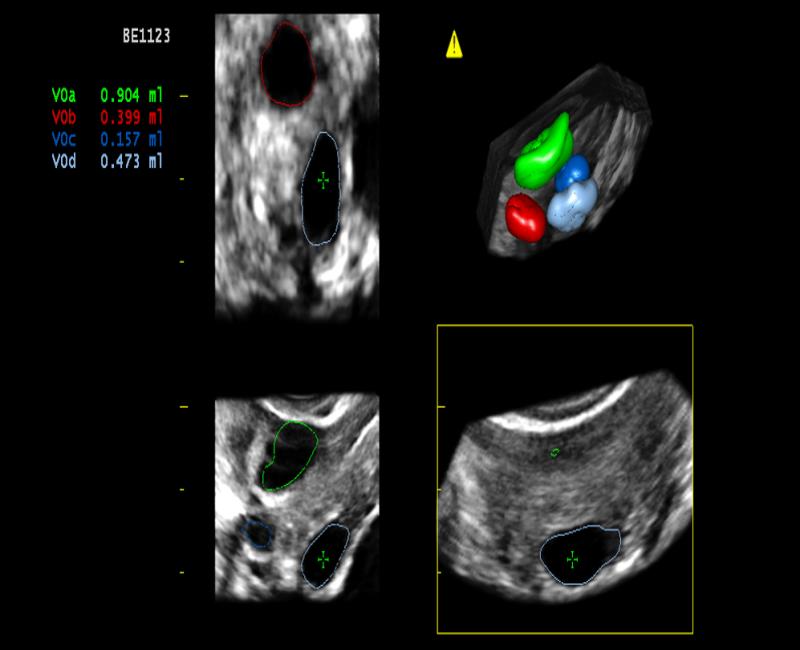

VRA - phần mềm tự động tính toán thể tích nang noãn.

may sieu am mylab x6